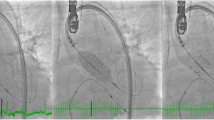

The HeartNavigator system (Philips Healthcare, Best Netherlands) is a proprietary software available for computed tomography-fluoroscopy fusion imaging in TAVR and utilizes the pre-procedural cardiac CT images [33, 34] (Fig. 2a–c). Pre-procedural 2D images are 3D volume-rendered and automatically segmented to identify the aortic root, coronary ostia, the aortic valve, the left ventricle, and the valve plane running through the bottom of the three cusps [35–37]. After segmentation, X-ray projections are planned by positioning a simulated X-ray view based on 3D-rendered images with the same perspective as that of the fluoroscopic c-arm. Views are selected such that the fluoroscopic image is in line with the valve plane. Aortic measurements and overlay of a virtual THV are then performed prior to implantation. Next, the CT images are registered with fluoroscopy and an outline of the cardiac structures with landmarks are subsequently overlayed onto the live fluoroscopic image to guide TAVR implantation.

a Computed tomography (CT)-fluoroscopy fusion imaging (Philips Healthcare, Best Netherlands) utilizes the pre-procedural CT images and volume-renders and automatically segments the aortic valve (green), aortic root/aorta with coronary arteries and bypass grafts (orange), and left ventricle (blue). b Generation of a valve plane running through the bottom of the three cusps is generated (yellow line) and appropriate c-arm angulations for implant determined. A virtual CoreValve is implanted to simulate size, implantation depth, and orientation. c CT overlay onto live fluoroscopy is shown for guidance during transcatheter heart valve implantation. d Transesophageal echocardiography (TEE)-fluoroscopy fusion imaging (Philips Healthcare) registers the TEE field of view with fluorosocopy. Landmarks placed, such as the annular plane (yellow circle) and left coronary artery (purple marker), are overlayed onto live fluoroscopy for additional guidance